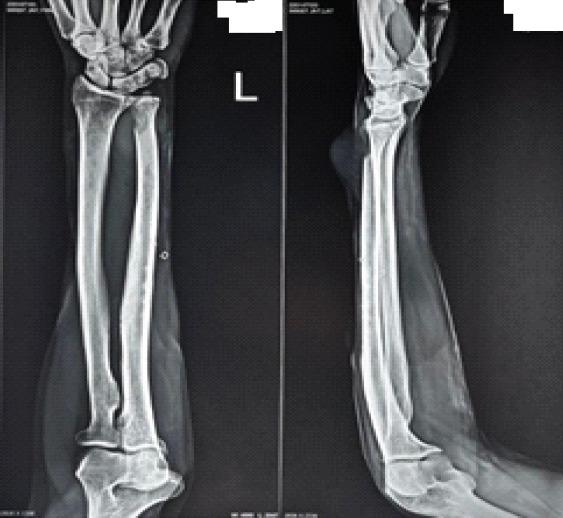

CASE REPORT

A 50-year-old man reported to outpatient department with a 5-month chief complaint of a painful mass involving his left carpus that had grown. No history of trauma was present. Examination demonstrated a painful restriction of wrist motions, and ill-defined, immobile, tender hard mass measuring 5 × 3 cm along the ulnar border of the left wrist. All necessary investigations were done and were diagnosed as primary leiomyosarcoma of the distal ulna. Patient was managed surgically with resection with wide en bloc resection with a margin of at least 2 mm around the tumor and radioulnar stabilization with the help of 1 K-wire (2.5 mm). Post-operative period was uneventful.

一名50岁男性因左腕部疼痛性肿块伴增大5个月就诊于门诊。无外伤史。检查发现腕关节活动疼痛受限,左腕尺侧缘有一5×3cm边界不清、固定、压痛的硬性肿块。完成了所有必要检查,诊断为尺骨远端原发性平滑肌肉瘤。患者接受了手术治疗,整块广泛切除肿瘤,肿瘤周围至少保留2mm切缘,并借助1根克氏针(2.5mm)进行桡尺骨固定。术后恢复顺利。